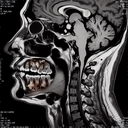

МРТ скронево-нижньощелепного суглоба

МРТ скронево-нижньощелепного суглоба (СНЩС) є неінвазивним діагностичним методом, який використовується для оцінки стану цього суглоба і прилеглих структур. Він надає детальні зображення м'яких тканин, що важливо для виявлення різних патологій. ### Коли використовують МРТ СНЩС: 1...